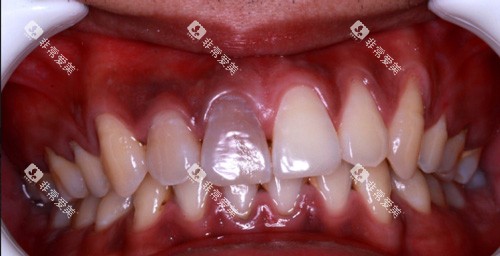

病例展示

在泰乐口腔的正式网站和线下门店,都展示了许多隐形矫正的成功病例。

这些病例涵盖了各种不同类型的牙齿畸形问题,如牙齿拥挤、龅牙、地包天等。

通过对比矫正前后的照片,可以明显看到患者牙齿的巨大变化。